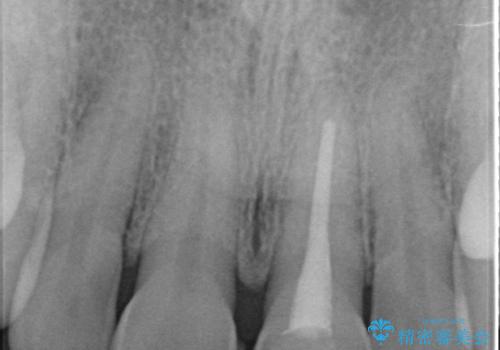

- 前歯の変色が気になるのでセラミックによる治療を行いたいといらっしゃった方の症例です。

左上1番目の歯の再根管治療終了後、左右1番目の2歯をオールセラミッククラウンで補綴しました。